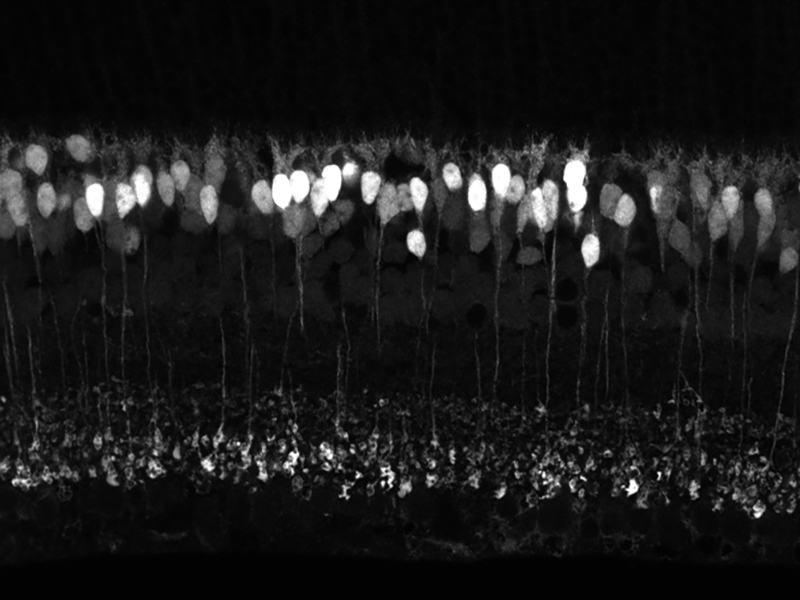

My research has centered on understanding the underlying cellular mechanisms and identifying novel treatments for neurodegenerative, neuromuscular, and inflammatory diseases. Most recently, I have been developing gene therapies for diseases that affect the eye like retinitis pigmentosa, uveitis, and age-related macular degeneration.

Earlier in my career I studied muscular dystrophies associated with mutations in dysferlin and members of the dystrophin-glycoprotein complex. While these are very different diseases from those that affect the eye, the underlying cell biology share common features. For example, inherited mutations can have a negative consequence on calcium signaling, cell membrane biology, or cytoskeletal dynamics, which ultimately cause different diseases depending on the cell type affected (i.e. muscle myofibers or retinal neurons).